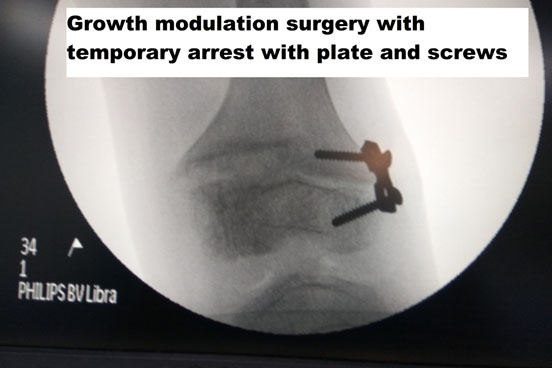

Growth Modulation

If there is adequate growth left ( age between 10-12 years), then the deformity can be treated with a simple surgery where the growth plates are temporarily held without growth by using plates that prevent bone from growing, and thereby deformity can be corrected.